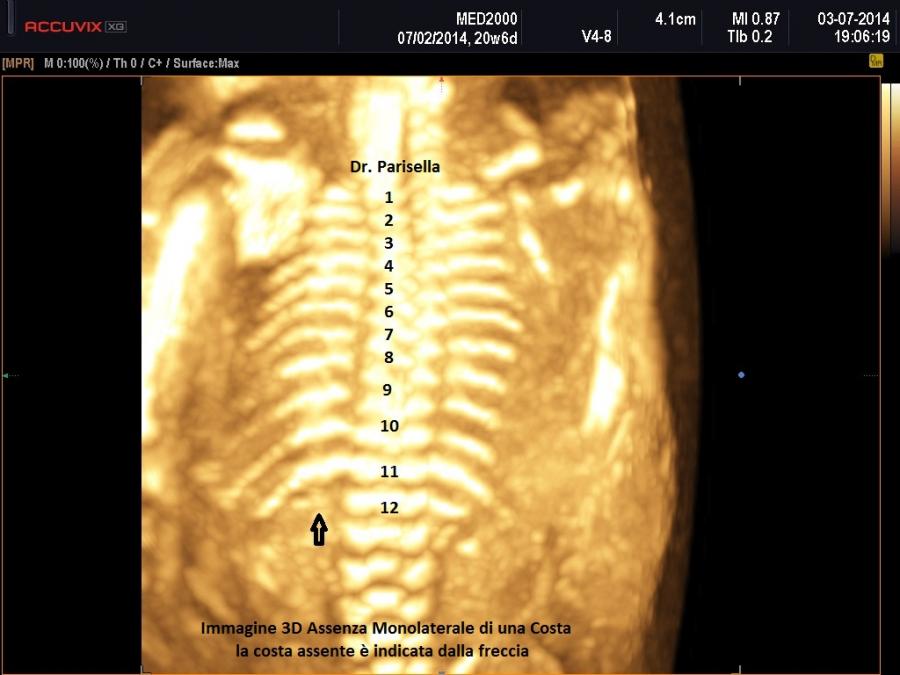

b.Coste: corte , ricurve, fratture

La misura della circonferenza toracica con un valore < 5° percentile è un indice di ipoplasia polmonare, causa di distress respiratorio nel neonato e indice di letalità. La biometria toracica e la morfologia toracica possono orientarci verso una particolare forma di displasia: se il torace è eccessivamente piccolo potrebbe trattarsi di una Displasia Tanatofora; se il torace è lungo e stretto potrebbe trattarsi di una Sindrome di Jeune; se le coste sono molto corte potrebbe trattarsi di una Sindrome coste corte con o senza polidattilia; se ci sono fratture costali potrebbe trattarsi di una Osteogenesi Imperfetta tipo II; se le coste sono fuse tra loro potrebbe trattarsi di una Displasia Spondilocostale.